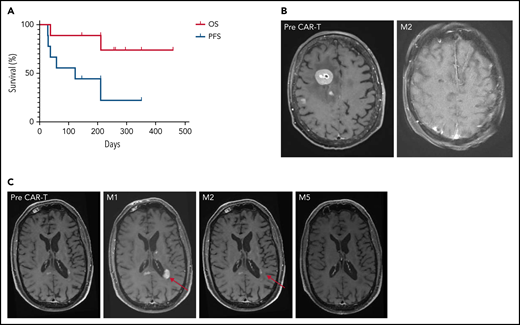

Survival and imaging of patients with R/R PCNSL treated with commercial anti-CD19 CAR T-cells. (A) OS and PFS. Median OS was not reached. Median PFS was 122 days for the whole cohort, increasing to 210 days for responders, vs 29 days for non-responders. (B) Patient 3: right frontal lesion at baseline and CR 2 months after CAR T-cell infusion. (C) Illustration of the flare effect suspected in patient 6: appearance of a left periventricular lesion 1 month after CAR T-cell infusion that dramatically decreased 2 and 5 months later. Despite high suspicion of a flare effect, response was reported as progressive disease according to the IPCG criteria, thus potentially underestimating PFS.

Patient 3 presented with high tumor burden and PD at time of CAR T-cell infusion, associated with an ocular infiltration. A remarkable response to CAR T-cells was observed, with a persistent CR on brain magnetic resonance imaging (MRI; Figure 1B). Because of a grade 4 ICANS with status epilepticus, an eye examination was not feasible. The level of interleukin-10 was measured at 1200 pg/mL in the anterior chamber at M6.16 A larger series is needed to evaluate CAR T-cell homing in the ocular compartment.

Patient 6 had an early brain MRI 9 days after CAR T-cell infusion because of clinical deterioration. New multiple contrast-enhanced nodular lesions of several millimeters were observed. On MRIs performed 7 and 19 days later, without any additional treatment, these lesions significantly decreased, but 2 new lesions appeared in the corpus callosum and left periventricular region (Figure 1C). These lesions then markedly decreased on subsequent MRIs at M2, M3, and M6. In parallel, clinical status dramatically improved, raising the potential of pseudoprogression linked to CAR T-cell therapy and the difficulty to assess the response.